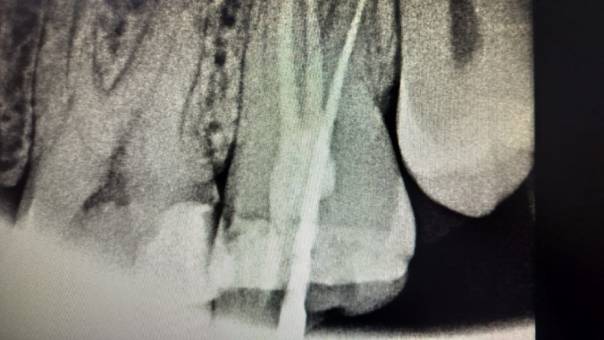

Clinical and Radiographic Findings:

On examination, mild tenderness was noted when

tapping on tooth 27. A radiographic evaluation

revealed that the distal canal of the tooth had been

inadequately treated and left unfilled. This had led

to a localized periapical infection.

Locating the distal canal